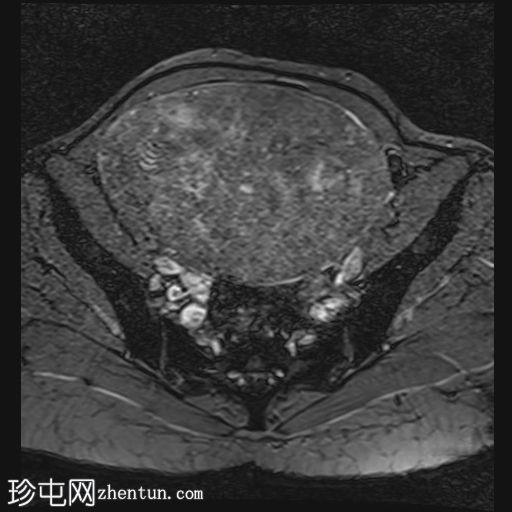

子宫后壁可见一个边界清晰、体积较大的浆膜下肌瘤,大小约为16.1 x 10.5 x 14.4 cm(宽 x 深 x 高)。

该肌瘤在T1加权像上呈中等信号,在T2加权像上呈低信号,内部区域呈囊性变性。

该肿块导致正常子宫结构严重变形。增强扫描显示轻度不均匀强化,未见弥散受限征象或提示恶性肿瘤的可疑强化。

双侧卵巢增大,各有超过10个卵泡,呈珍珠串状排列,周围未见优势卵泡。这些发现符合多囊卵巢的形态学特征。